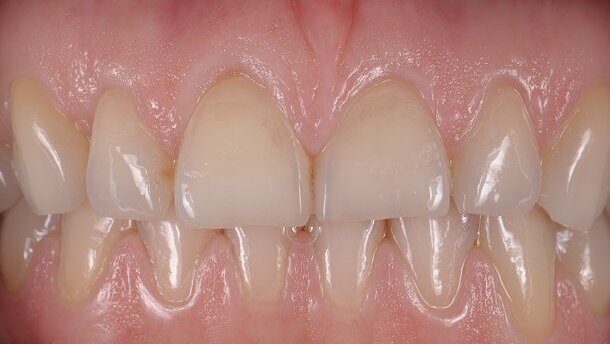

_Fig. 1a : Situation initiale avec érosion et usure de 11 et 21. Cette usure de nature chimique a essentiellement entraîné une perte verticale des tissus, d’où une perte de dominance dans le sourire, ainsi qu’un manque de substance vestibulaire.

_Fig. 1b : Vue à plus fort grossissement des centrales maxillaires.